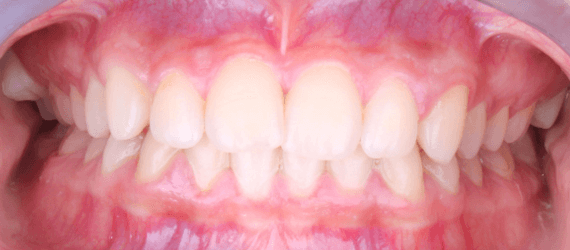

13 de mayo de 2025

Se cambió el arco superior a un rectangular de NiTi 16x22". Se recementó el botón palatino del órgano dentario 47 (OD 47), el cual se había despegado. Se mantuvo el arco inferior sin modificaciones. Hasta esta fecha, los órganos dentarios 17 y 27 continúan fuera del arco, ya que su ingreso se está realizando mediante movimientos individualizados. Se continuó con el uso de elásticos cruzados de 1/8" y 2.5 onzas.

10 de junio 2025 (figura 13)

Se retiraron OD# 18 y 28 el dia 15 de mayo; en su cita de ajuste seretiró el ATP y se colocó tubo en el OD#27 para ingresarlo al arco, el #17 continua con bio ecanica de elasticos cruzados 1/8 2.5oz.